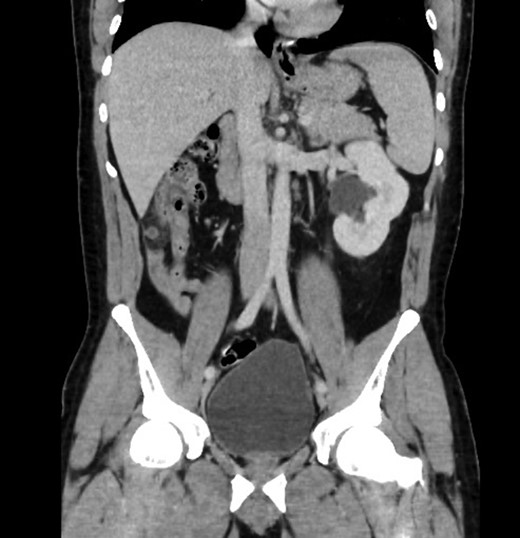

Upon review and clinically examination, the possibility of atypical appendicitis was raised due to the clinical history. Patient did not have any history of biliary colic or any epigastric pain. He was further investigated with CT abdomen which revealed the diagnosis of acute appendicitis in the right upper quadrant (Fig. 1). The atypical position of his presentation was a result of congenital right renal agenesis (Fig. 2). The appendix was lying on the right upper quadrant due to the absence of right kidney. He also had left kidney hydronephrosis and hypertrophy.

Sagittal view showing mal-descend of caecum secondary of congenital agenesis of right kidney, this resulted in subhepatic appendicitis.